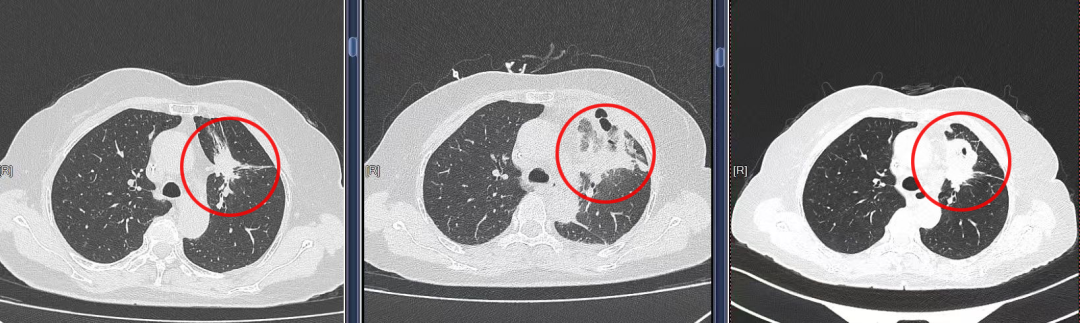

患者沈女士(化名)早在2021年便在昆山市中医医院胸外科确诊左上肺腺癌。经过靶向药物治疗,她的病情一度得到控制。但在近期复查时,胸部CT提示病灶进展,常规方案需进一步化疗。由于难以耐受副作用,她选择暂缓治疗。焦虑与担忧笼罩着她和家人,他们带着迫切的心情找到胸外科朱震主任医师,希望能找到新的办法。

手术当天,在CT实时引导下,穿刺针顺利进入肿瘤核心区域。随着微波能量释放,局部迅速形成高温场,短短数分钟便覆盖了整个病灶。沈女士全程清醒,仅接受局部麻醉,呼吸平稳,术中配合良好。术后恢复顺利,第四天即可出院。随访影像显示,消融区肿瘤完全坏死,这一结果让她和家人如释重负。

类似的经历也发生在张先生(化名)身上。他在体检中发现左肺上叶结节,进一步确诊为肺癌。因年事已高,且合并心脏疾病,常规手术风险极高。经过团队讨论,他接受了微波消融治疗。术后随访显示病灶得到有效控制,生活质量保持稳定。张先生感慨道:“没想到不开胸,也能治疗,而且恢复得这么快。”

▲胸外科赵建华医师为患者行CT引导下肺微波消融术